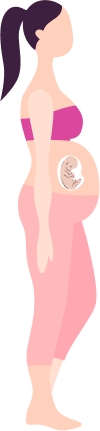

Taking Care of You and Your

Baby Pregnancy Timeline